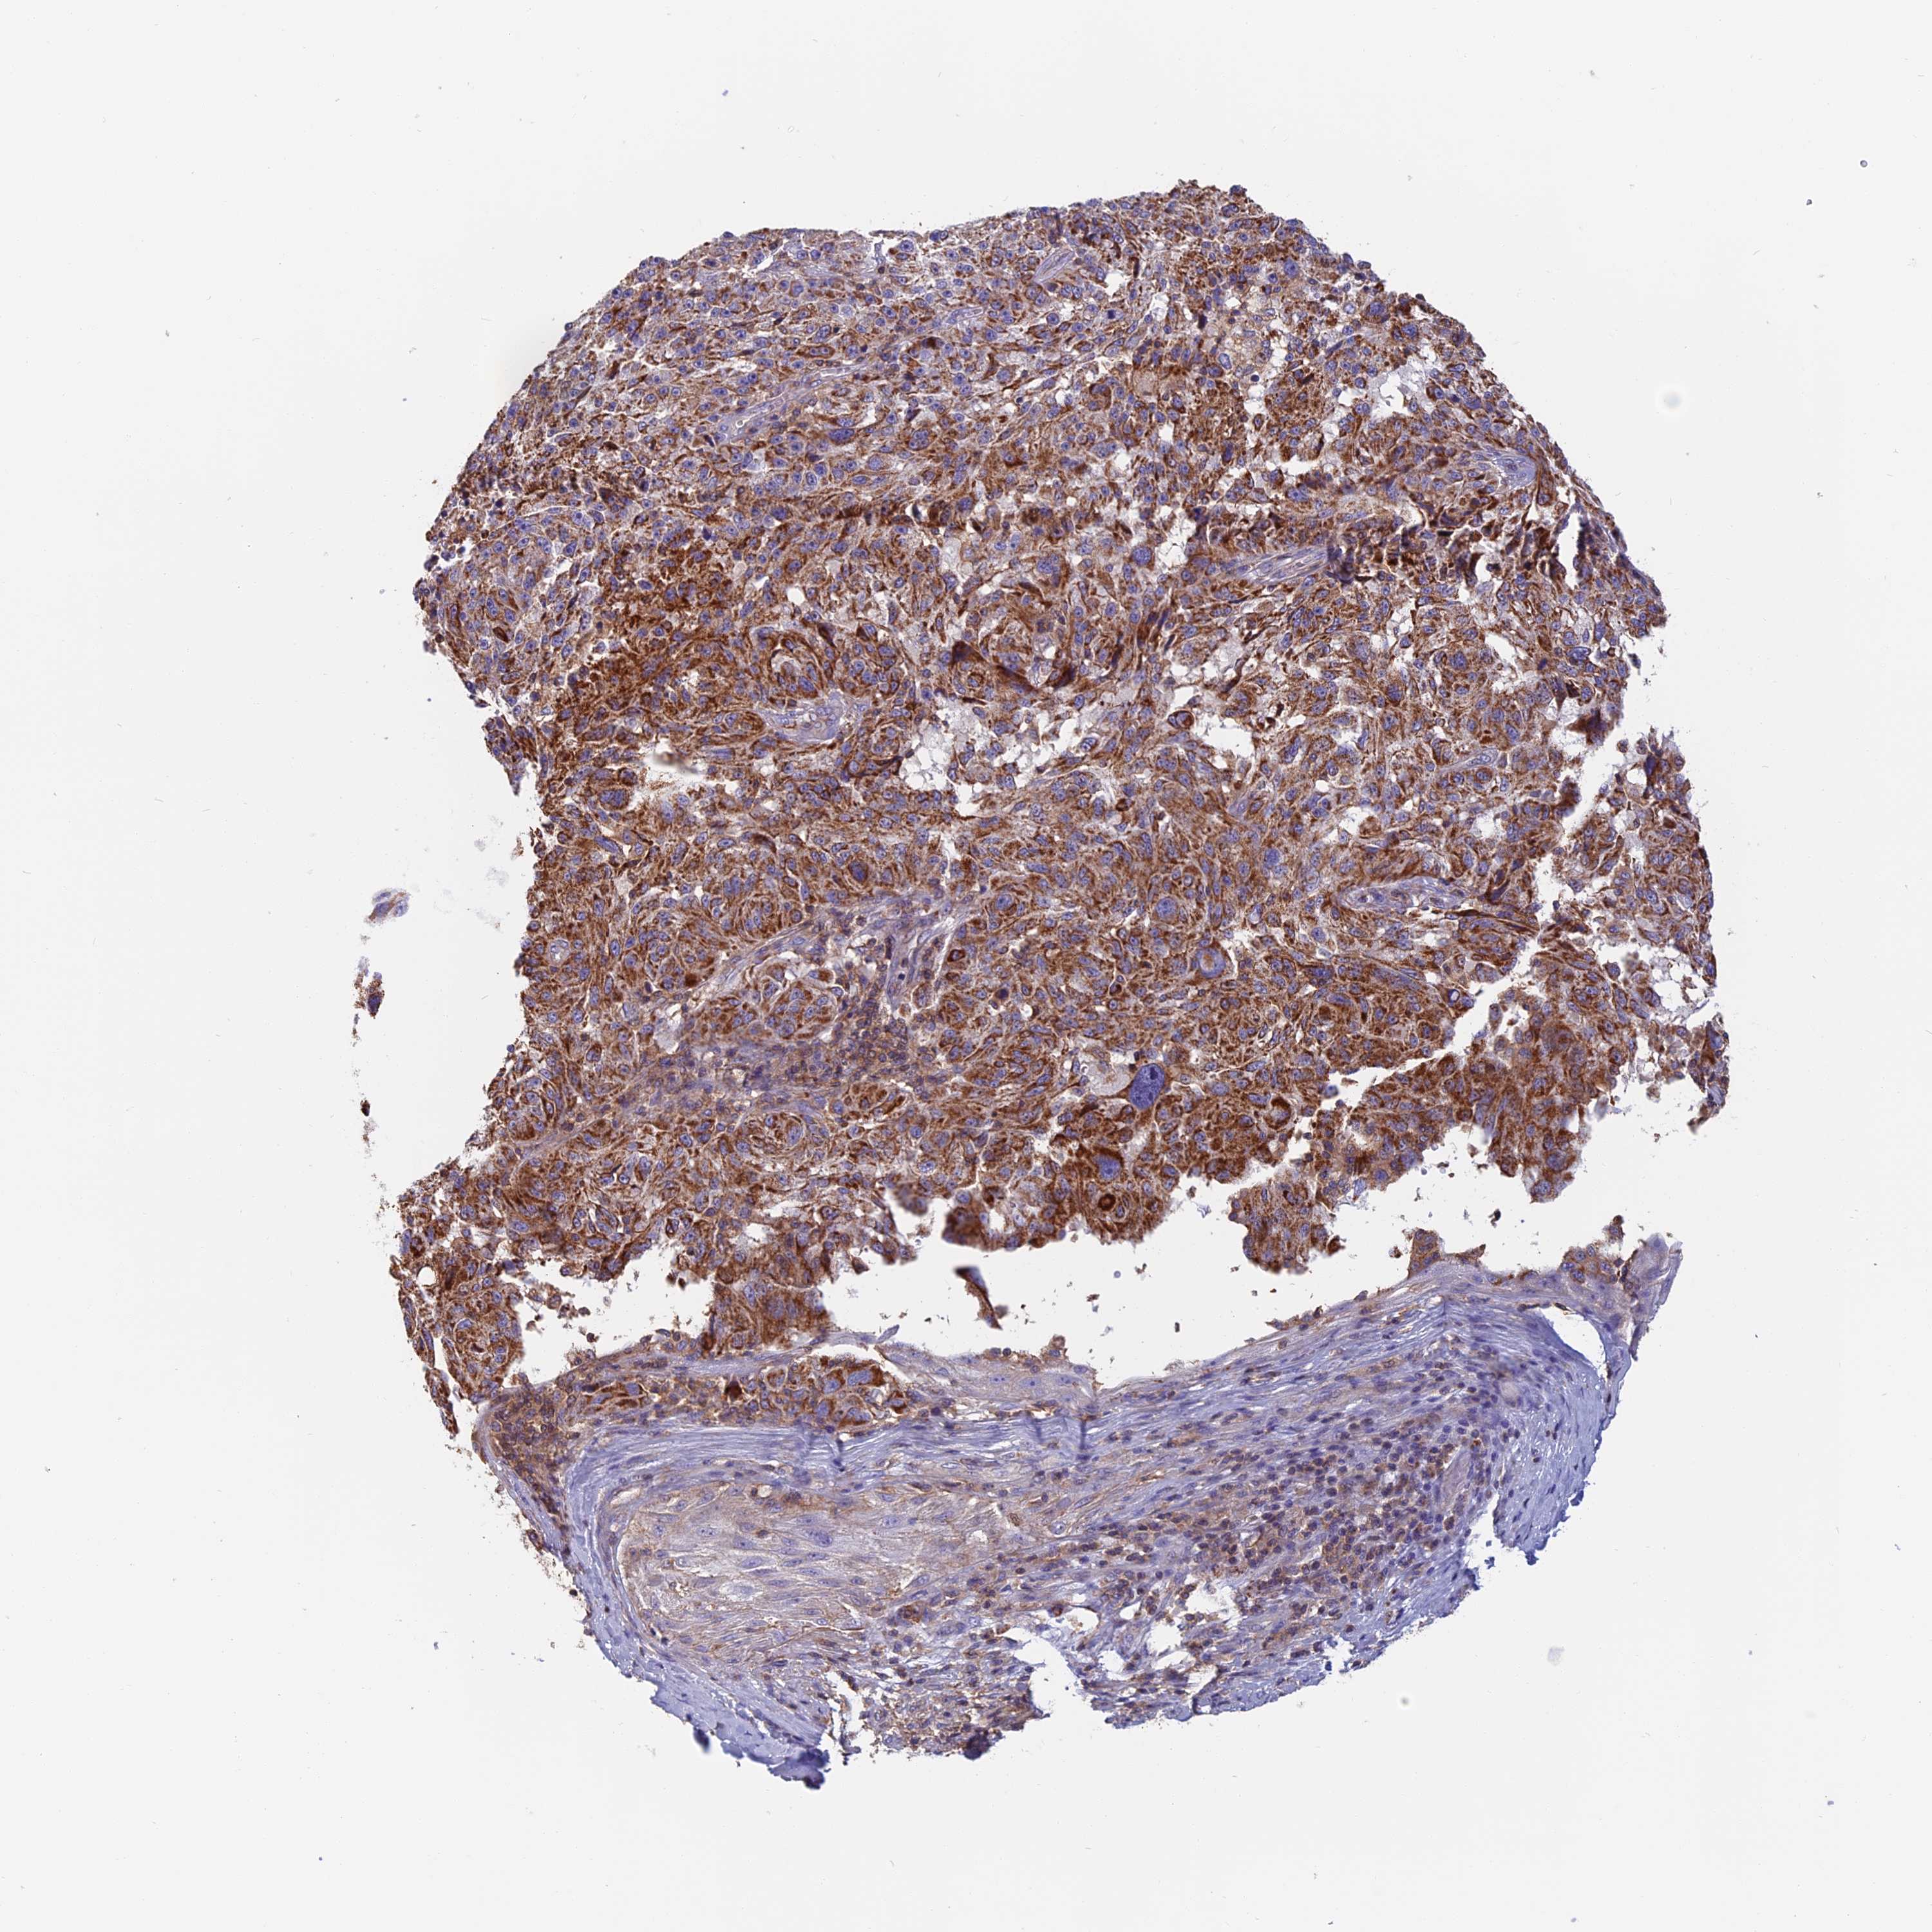

MELANOMA - Protein expressioni

A mouse-over function shows sample information and annotation data. Click on an image to view it in a full screen mode. Samples can be filtered based on level of antibody staining by selecting one or several of the following categories: high, medium, low and not detected. The assay and annotation is described here.

Note that samples used for immunohistochemistry by the Human Protein Atlas do not correspond to samples in the TCGA dataset.

Antibody stainingi

Antibody staining in the annotated cell types in the current human tissue is reported as not detected, low, medium, or high, based on conventional immunohistochemistry profiling in selected tissues. This score is based on the combination of the staining intensity and fraction of stained cells.

Each image is clickable and will lead to virtual microscopy that enables deeper exploration of all samples and also displays staining intensity scores, fraction scores and subcellular localization as well as patient and tissue information for each sample.

Antibody HPA042132

Malignant melanoma, NOS

Malignant melanoma, Metastatic site